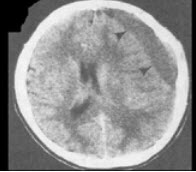

九个月男孩,头明显增大,前囟大而且鼓出,头下垂,双眼有落日征,头部叩诊有破壶音。四肢活动少,双侧Babinski征阴性,体温正常。

(单选题)根据CT表现可能的诊断( )

A:先天性脑积水